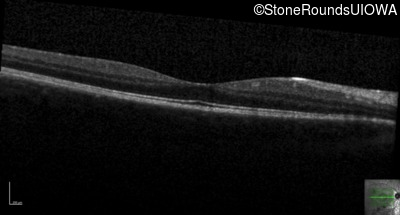

Optical Coherence Tomography - Left - 20/20 -1

Exemplar / OCT Stack

OCT Stack